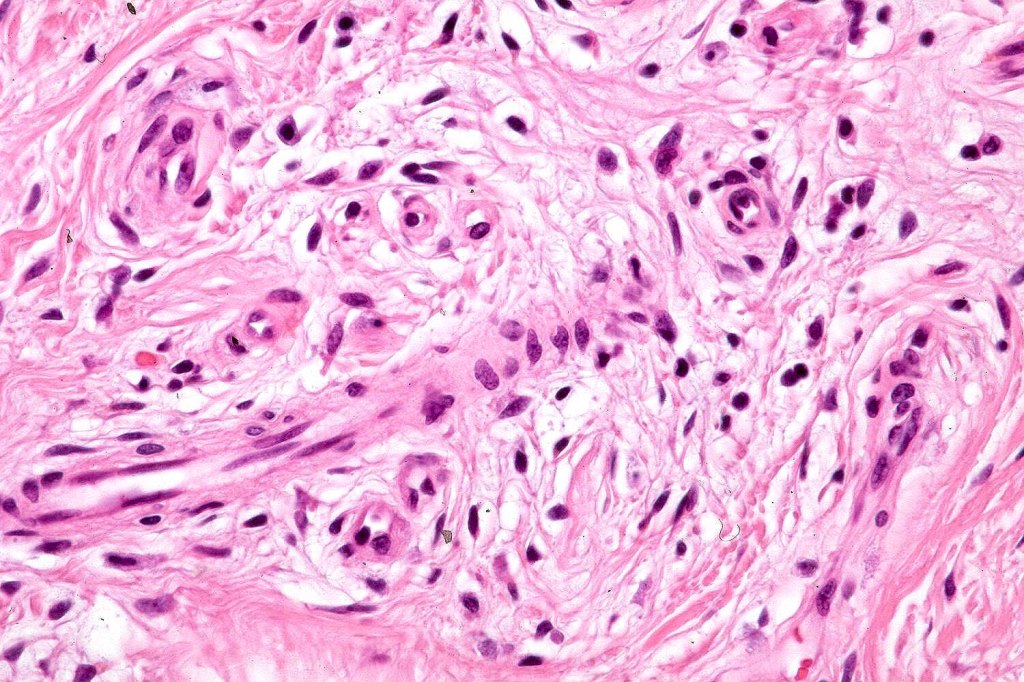

•An infundibular cyst is surrounded by laminated dermal collagen, elastic fibers, blood vessels, adipocytes & spindle cells separated from the adjacent dermis by a retraction artifact

•Exceptionally may show spindle cell lipoma-like features

•Exceptionally includes a neural component